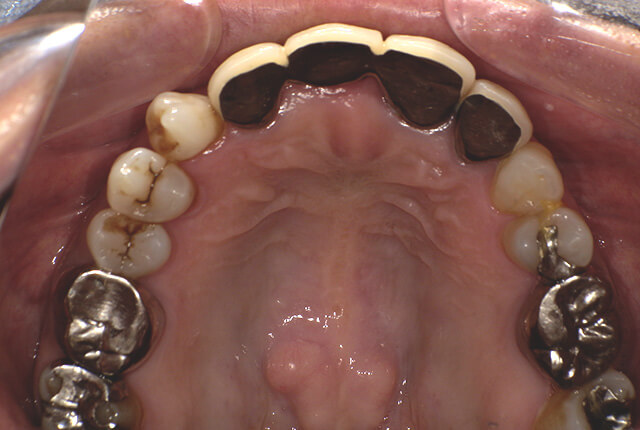

よく噛めず笑うと銀歯が目立つので気にされていました。

| 主訴 | ブリッジ脱離、しっかり噛めない |

| 診査診断 | 上顎歯牙欠損、歯周病、不良補綴、根尖性周囲炎。 不正咬合により噛み合わせのバランスが悪い事が原因により咬合治療が必要。 |

| 主訴 | 噛めない、食事がしっかりできる様になりたい。 |

| 診査診断 | 歯周病、歯の崩壊、不良補綴。 全顎的咬合異常、前歯の噛み合わせ、奥歯の噛み合わせに問題あり。 |